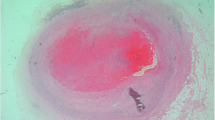

Neither calcifications nor adhesions were found on the epi- and pericardium. The entire epicardium was covered with a white massive fibrillary coating; loose precipitates of the coating are apparent as flocs freely floating in the conservation fluid. Numerous small villi on the cardiac surface showed features of fibrinous pericarditis. The most prominent lesions found were three small nodules, between several millimeters up to 1 cm in diameter, of white-glass appearance: two of them on the upper part of the right ventricular wall, one located closer to the apex of the heart, most likely of tuberculous origin.

The nodules present on the surface of Chopin’s heart look like myocardial tuberculoma described previously (Rosenbaum and Linn 1948). With the current level of TB therapy, such advanced organ lesions do not occur in well-developed countries. Similar lesions may also occur in the course of sarcoidosis, but this cause would not be justified in context of Chopin’s medical history.

The formation of such nodules and tapestry-like white coating by post mortem processes was ruled out (Witt et al. 2018b). These lesions, on closer inspection, differ significantly from focal mold colonies and deposits of inorganic crystals. Mold colonies are characterized by well-defined sharp edges; crystals appear only locally as separate foci; they also differ entirely from local lipid deposits. Such lesions occur mainly in old objects with significantly decreased levels of conservation fluid which was not the case for Chopin’s heart. White epicardial coating was widespread fairly evenly over the surface and was clearly visible regardless of the angle of observation, being a proof of an inflammatory process affecting the entire organ. Such morphology makes up the picture of fibrinous pericarditis, described in some sources as frosted heart or bread and butter appearance. The epicardial morphology argues for a short duration of pericarditis with a rapid progression. In contrast, prolonged tuberculous pericarditis is characterized by pericardial calcification with adhesions and is usually constrictive in nature (pericarditis constrictiva).

The morphologic data obtained in our study (Witt et al. 2018a,b), described exclusively by us, and the data from the composer’s natural history indicate with high probability that in the last period of his life Frederic Chopin suffered from severe fibrinous pericarditis, as evidenced by fibrinous deposits on its surface, foci of hyalinization, focal hemorrhagic effusions on the left ventricular anterior wall, dilatation of mainly the right ventricle and probably the right atrium, indicative of the right ventricular chronic heart failure. We can state with high probability that for Chopin, his active tuberculosis was complicated by pericarditis which thus should be considered tuberculous pericarditis (pericarditis tuberculosa). It is one of the most severe organ complications of disseminated tuberculosis, characterized by extremely poor prognosis (Mayosi 2009). Fibrinous deposits on the epicardium, together with hemorrhagic effusions that sometimes appear, are specific especially for a subacute or early chronic phase of the disease (Mayosi 2009; Kotharii and Roy 2009; Tavora and Burke 2017).